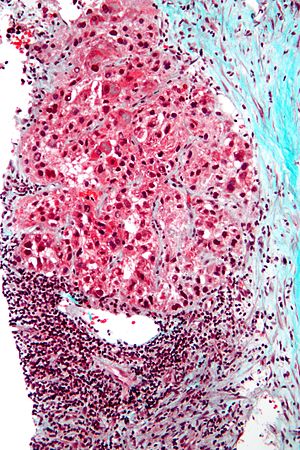

Hepatocellular carcinoma with acini. A. Fibrous bands dissect hepatocyte nodules, mostly hepatoma. B. The fibrous band on right bears proliferating bile ductules; acinar arrangement on left shows holes much larger than canaliculi. C. The tumor has cancerous nuclei; note the bile which makes for absolute diagnostic certainty [arrow]. D. Noncancerous hepatocytes on left can be compared with tumor cells on right. Note increased nuclear crowding & a subtle increment in cytoplasmic basophilia in tumor.